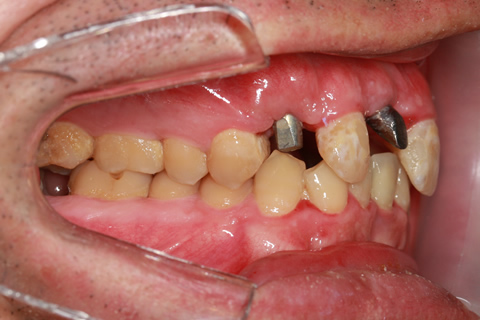

症例3

治療前

インプラント埋入時

治療後

- 年齢・性別

- 60歳男性

- 治療期間

- 2ヶ月

- 抜歯

- なし

- 治療費

- 61.6万円

- 備考

- 右下6.7欠損

- 治療内容

- 右下6.7欠損部にインプラント埋入

- 施術の副作用(リスク)

- オペによる知覚障害。インプラントによる歯肉炎。インプラント脱落。